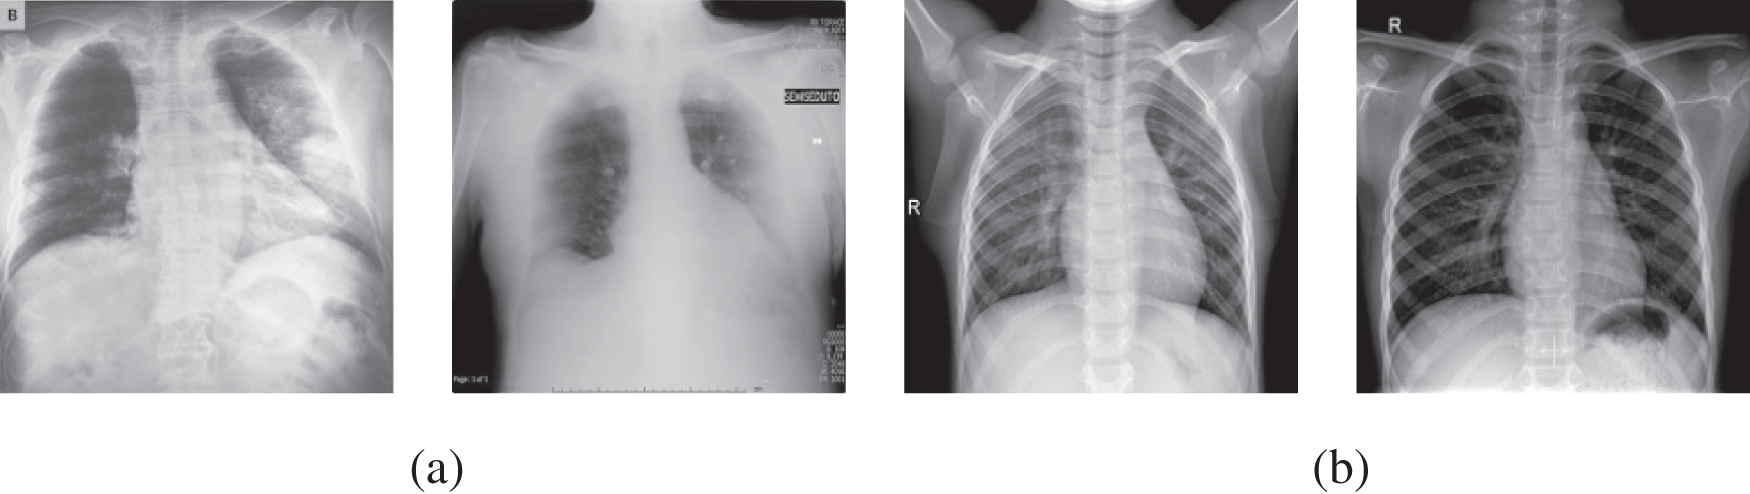

As the dataset is compiled from various sources, the images’ sizes vary. The images’ size related to COVID-19-affected patients varies from 157 × 156 to 5623 × 4757 pixels, whereas the images downloaded from NIH-USNLM are 3000 × 3000, 4020 × 4892, or 4892 × 4020 pixels, while images from the third source vary from 994 × 758 to 2572 × 2476 pixels. To bypass the effect of image size on classification performance, the collected dataset images were normalized to 224 × 224 before feeding into the proposed system. Fig. 2 depicts X-ray image samples of COVID-19 affected patients and normal healthy patients, whereas images from NIH-USNLM about TB and normal patients are not depicted in Fig. 2 due to copyright and privacy agreement.

Figure 2: Instances of radiography images data set utilized for recommended framework, (a) COVID-19 positive cases, and (b) normal cases